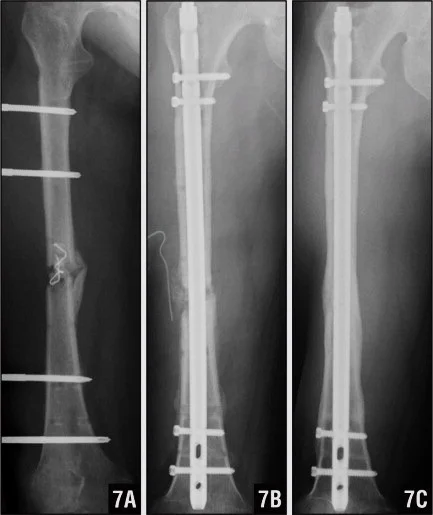

Femoral Shaft Fractures

Mechanism and Complications

- Mechanism: high energy

- Bleeding:

- Can easily loose 2L of blood

- Need good resuscitation

- Early fixation

- Inability to bear weight

- Risk of thrombo-embolism

- X-rays:

- AP & lateral radiographs

- Two joints (above and below)

- Very important

Surgical Treatment

- IMN: Intramedullary nail / Locked(with screws)

- The treatment of choice

- Relative stability

- Allows early weight-bearing

Intramedullary Nailing

- IMN: Intramedullary nail

- Locked IMN (with screws)